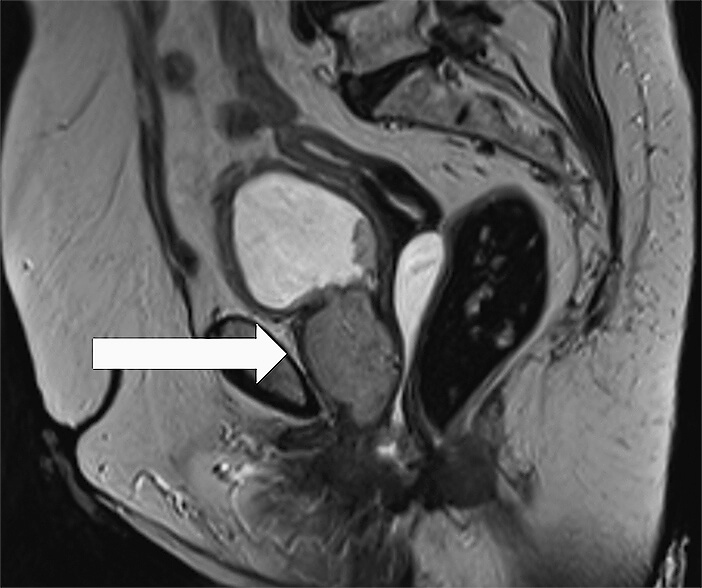

Eine 85-jährige Patientin stellte sich 08/2021 in unserer Klinik wegen einer schmerzlosen Makrohämaturie vor. Zystoskopisch zeigte sich ein Harnröhrentumor, der transurethral reseziert wurde. Histologisch wurde zunächst ein nephrogenes Adenom diagnostiziert. 11/2021 stellte sie sich wegen eines Harnverhalts und lokalen Tumorwachstums erneut bei uns vor. Es erfolgte zur Schonung des Kontinenzmechanismusses nur eine partielle transurethrale Resektion. Histologisch zeigte sich das vorbeschriebene nephrogene Adenom. Aufgrund der in der Literatur für diese Tumorentität beschriebenen hohen Rezidivrate besprachen wir das weitere Procedere in unserem interdisziplinären Tumorboard. Es wurde sich für eine möglichst komplette transurethrale Resektion bei bis dato benigner Erkrankung ausgesprochen. Im Vorfeld erfolgte eine MR-Bildgebung 01/2022 (▶ Abb. 1, 2). Dabei zeigte sich ein ausgedehnter zirkulärer Tumor, der auf der gesamten Länge der Urethra wuchs und den Blasenhals infiltrierte (Tumorausdehnung 4 x 3,3 x 6,6 cm mit deutlichem Kontrastenhancement der Tumormasse). Zudem wurde der Verdacht auf eine lokoregionäre Lymphknotenmetastase an der linken Scheidenwand (2,2 x 1,3 cm) geäußert.